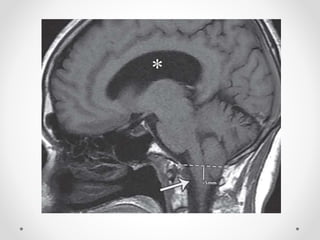

3. Thoát vị hạnh nhân

- Hạnh nhân tiểu não xuống thấp so với lỗ chẩm

=> Thân não hạ thấp, trung tâm hô hấp và tim mạch bị đè

ép vào bản dốc xương chẩm

- Nguyên nhân: giai đoạn sau của DTH, tăng áp lực hố

sau, chọc dò tuỷ sống dẫn lưu dịch não tuỷ...

CĐHA:

• Hạnh nhân tiểu não trở nên dẹt, nhọn, lồi xuống >3 mm

so với đường McRae line (tuỳ tác giả)

• Xoá bể lớn

• Ứ nước não thất do chèn vào não thất IV

• Nhồi máu tiểu não nếu chèn ép ĐM tiểu não sau dưới